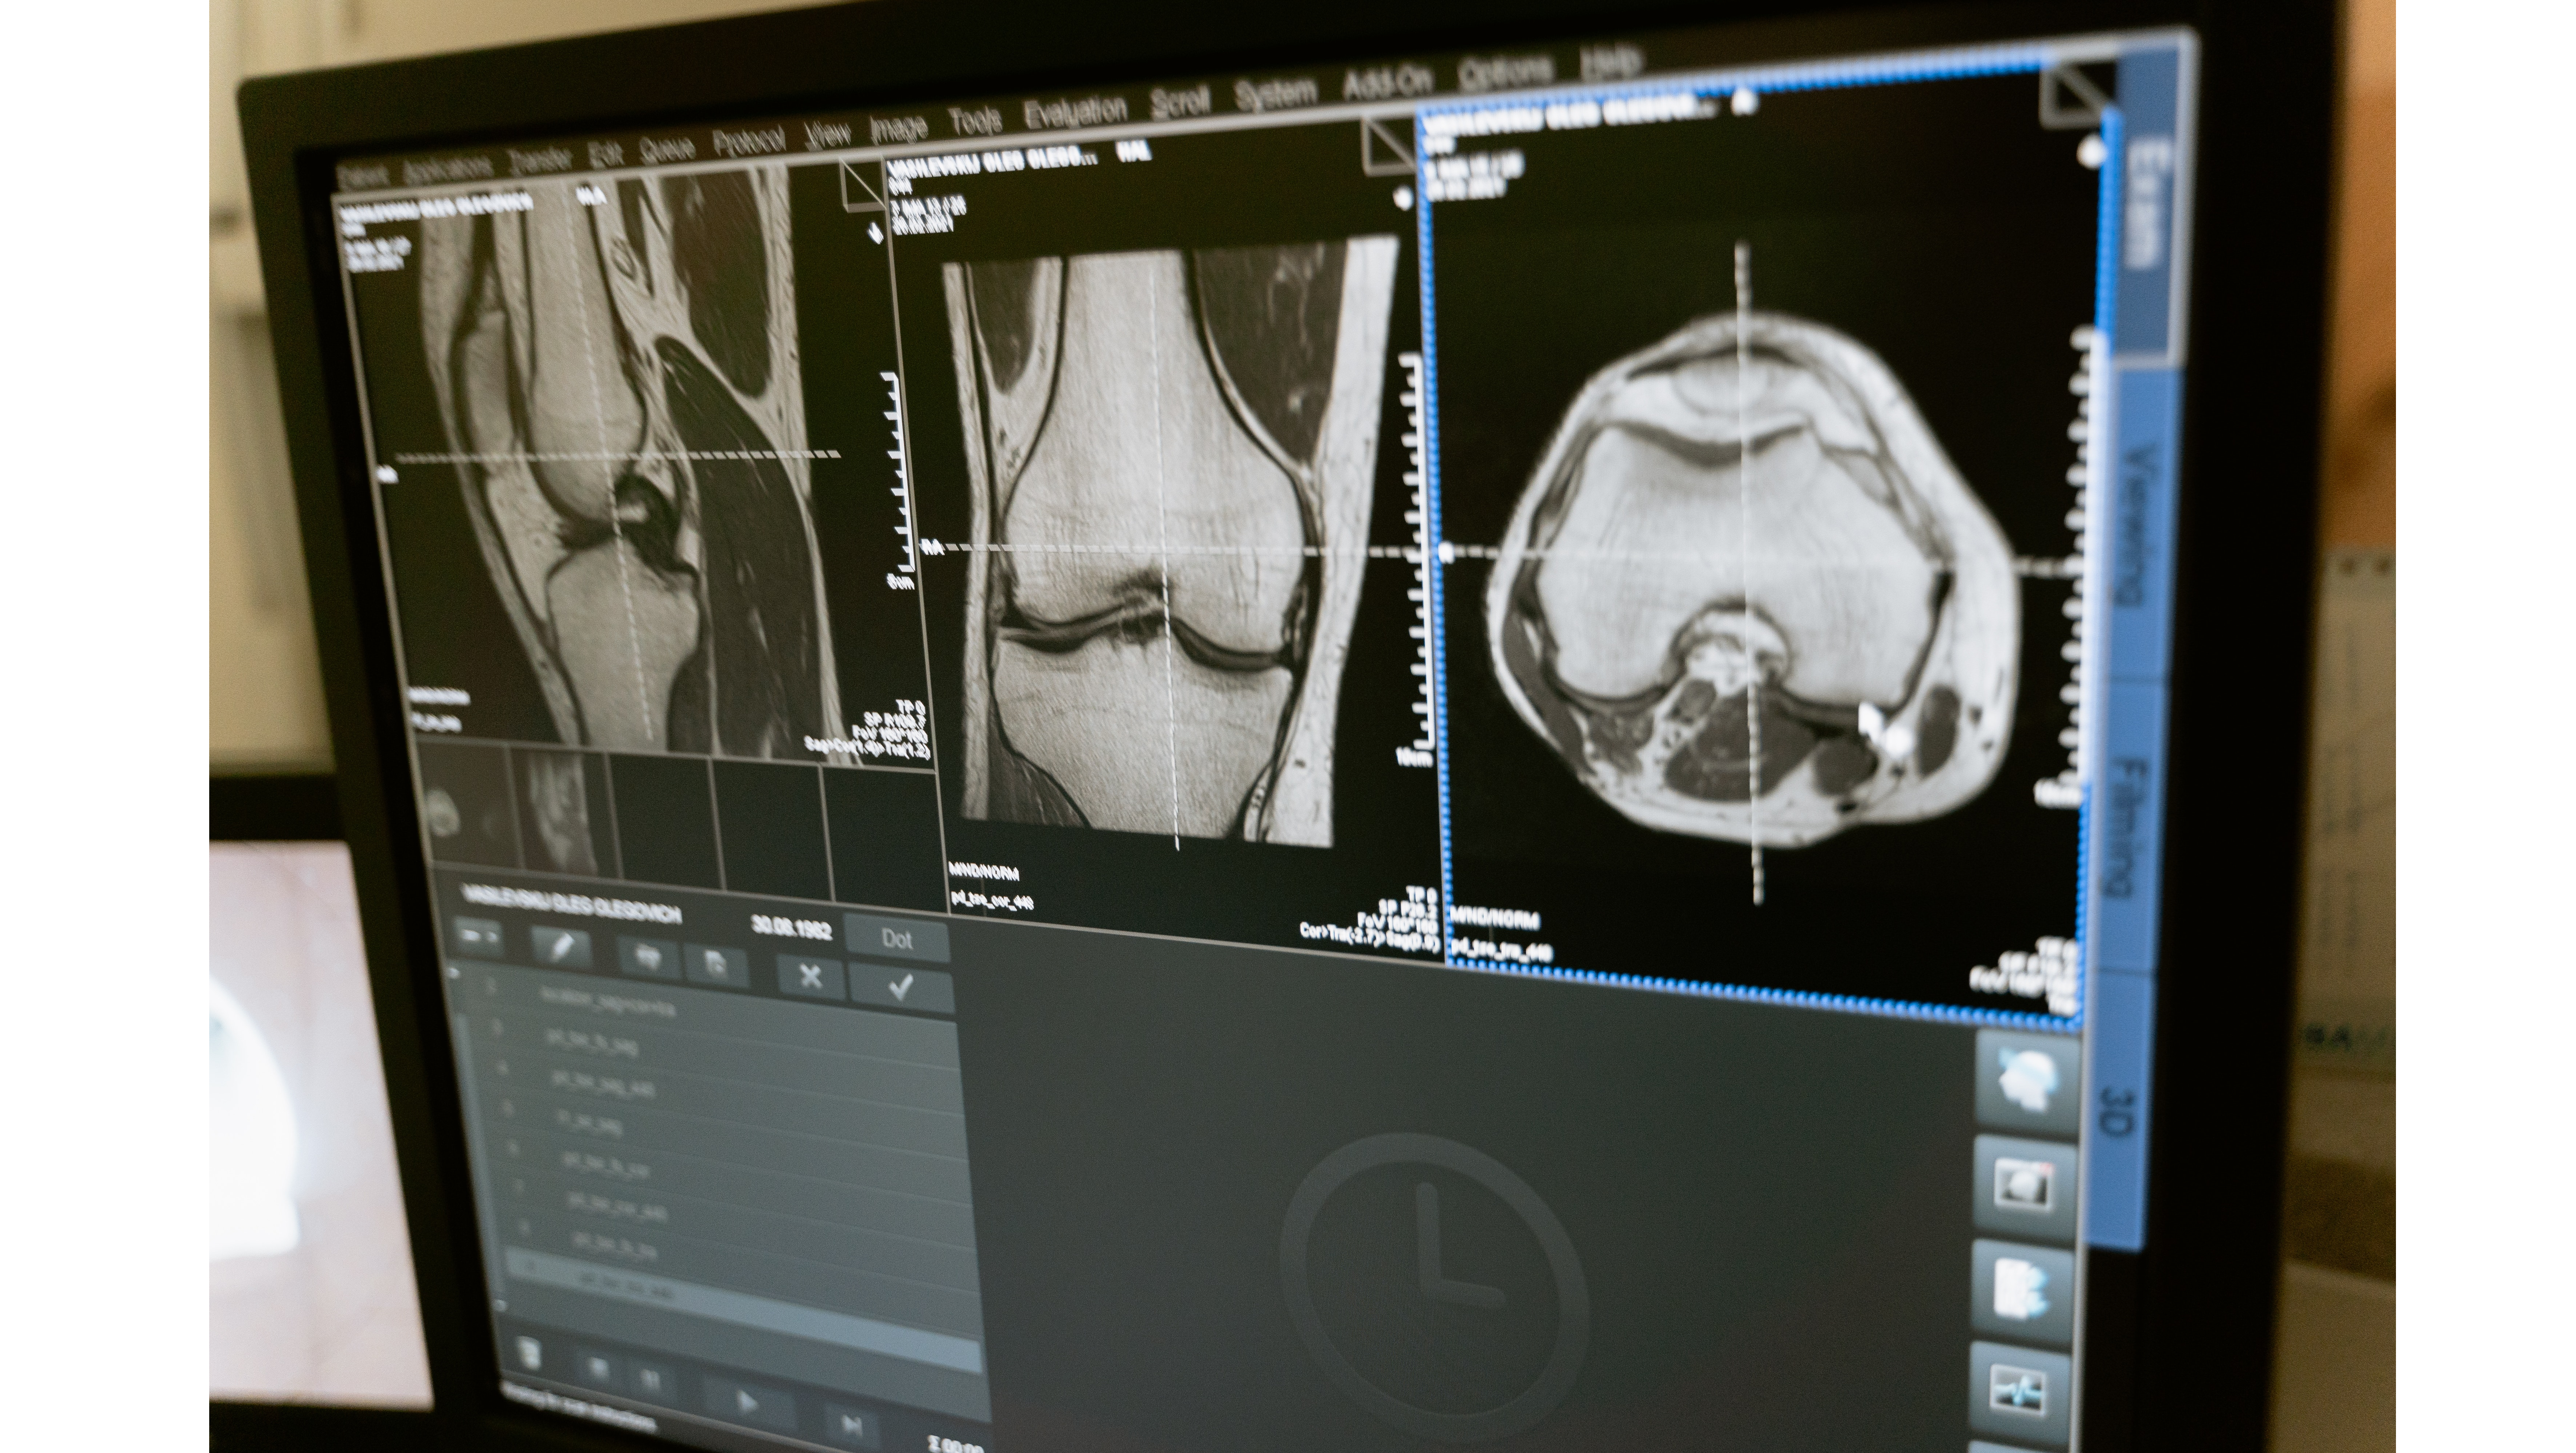

Le docteur Vincent Paoli est ancien interne chef de clinique des hôpitaux de Lyon. Aujourd’hui, il a associé dans le groupe IMACAM qui compte 30 radiologues répartis sur 7 centres à Montpellier. Pour lui, la radiopédiatrie a toujours été une évidence même si selon lui c’est aussi une histoire de rencontres avec une équipe charismatique et enthousiaste qui lui a donné envie de pratiquer cette surspécialité. La radiopédiatrie est pratiquée dans des villes de taille conséquente et dans des groupes d’imagerie libérale de taille moyenne à grande qui permettent à chacun de pratiquer sa surspécialité. Surtout, il faut s’assurer que son groupe est adossé à une clinique avec un service pédiatrique, une maternité, etc. Si vous aimez être en contact avec les patients, la radiopédiatrie est fait pour vous ! Comme le précise le docteur Paoli : « Les radiologues ont tendance à voir de moins en moins les patients, en radiopédiatrie c’est impossible. Il faut passer du temps avec les jeunes patients et leurs parents. ». La radiopédiatrie n’est pas axée sur un organe mais sur un être humain dans son ensemble, elle est donc très vaste et nécessite d’être très polyvalent. Elle permet aussi au groupe d’imagerie d’entretenir de bonnes relations avec ses correspondants et les centres de soins de proximité. Au sein du groupe IMACAM à Montpellier ou s’est associé le docteur Vincent Paoli, une IRM a été adaptée aux enfants et permet de diffuser des soins pendant l’examen. Choisir la radiopédiatrie, c’est choisir une spécialité qui a du potentiel dans les années à venir. En effet, avec les regroupements des groupes d’imagerie en libéral, les radiologues peuvent s’organiser pour pratiquer leur surspécialisation. La radiopédiatrie encore une fois, reste une spécialité complexe et vaste, peu préemptée à tort par les jeunes. Néanmoins, quand on a la fibre avec les enfants et qu’on a à coeur de valoriser la relation soignants/ soigné c’est une spécialité grisante. Choisissez bien votre environnement pour vous installer, c’est le conseil du docteur Paoli. Le libéral a besoin de vous !

À Reims, le docteur Gratiela Mac Caby a opté pour une activité mixte. En 2009, elle a repris, à l’hôpital, l’activité pédiatrique d’une radiologue qui partait en retraite. Elles étaient deux jeunes radiologues à l’époque à être arrivées au sein du service. Comme elle le précise : « Au début, on appréhende la radiopédiatrie car c’est un peu stressant de s’occuper des enfants mais au fur et à mesure on finit par adorer. C’est une surspécialité au sein de laquelle on ne s’ennuie jamais car d’un patient à l’autre, on ne pratique jamais le même acte. On explore tous les étages et c’est très très enrichissant ». Le docteur Gratiela Mac Caby ne regrette pour rien au monde ce choix de surspécialité qu’elle défend. Elle a décidé de garder une activité mixte hospitalière et libérale au sein du groupe PRIM, membre du réseau Vidi, à Reims. En libéral, la radiopédiatrie est moins représentée car elle nécessite une organisation dédiée, notamment pour la prise en charge de jeunes enfants en IRM où plus de temps est nécessaire. Le docteur Mac Caby invite les jeunes internes à découvrir cette surspécialité en se donnant la chance de faire un stage dans un service dédié à la radiopédiatrie qui est souvent très formateur et révélateur de vocation. La radiopédiatrie est une surspécialité très valorisante, la petite communauté de radiopédiatres est très investie dans la prise en charge des pathologies des enfants, du plus petit, même avant la naissance par l'imagerie anténatale jusqu'aux plus grands. Une découverte et une prise en charge précoce de certaines pathologies comme par exemple la scoliose, peuvent réduire considérablement des problèmes de santé à l'âge adulte. Pour le groupe d’imagerie, c’est une très belle vitrine que de proposer cette surspécialité. Elle insiste sur les liens essentiels à entretenir avec les pédiatres et les généralistes mais aussi sur la nécessité d’avoir la capacité d'être à l'écoute des parents stressés avec des enfants souffrants. Enfin, elle invite les jeunes de l’UNIR à participer à tous les évènements organisés par la SFIPP : https://sfip-radiopediatrie.org/ afin de faire en sorte que la radiopédiatrie soit toujours représentée au sein des groupes d’imagerie et des établissements de santé sachant que la population des 0-19 ans représente 25 % de la population. N’hésitez pas à la découvrir à l’occasion d’un stage et d’aller à la rencontre de cette communauté de radiopédiatres enthousiastes et très investis !